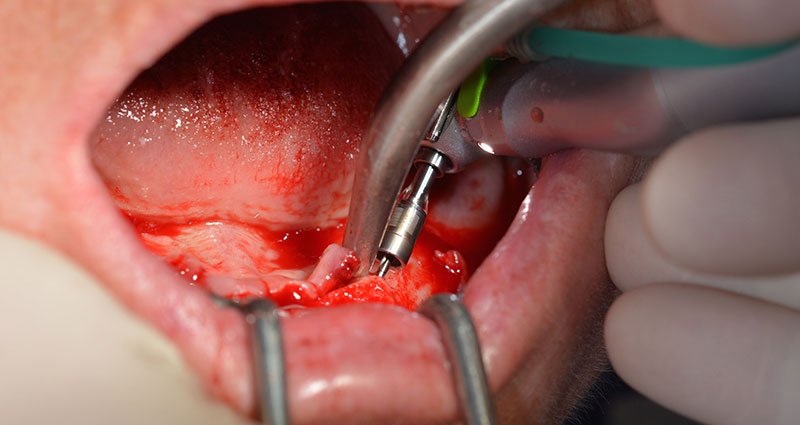

This is where the first advantages of Implantmed become obvious. The surgical protocol is already preset and the settings stored at fixed positions. The individual positions can be selected by simply pressing the “P” position on the foot control or via the display itself. The preset speed of 35,000 rpm in position 1 in this case is also shown in large figures on the illuminated display (Fig. 5 and 6).

The surgical protocol for the implants employed (SKY, bredent medical) specifies a speed of 1,200 rpm for the pilot drilling (Fig. 7 - 9).